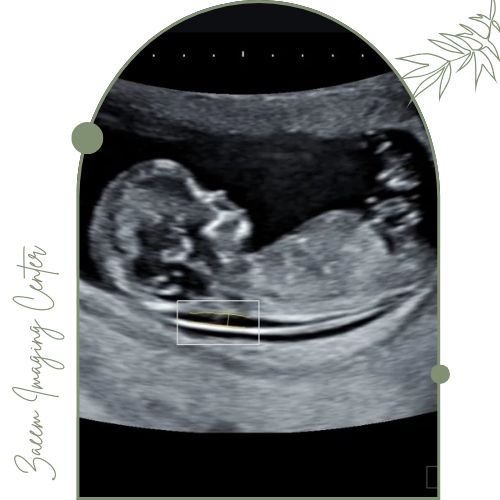

در این مرکز از دستگاههای پیشرفته سونوگرافی ویژه NT استفاده میشود. این تجهیزات تصویری کاملاً واضح از ضخامت شفاف پشت گردن جنین (NT) و سایر شاخصهای مهم سلامت جنین بهدست میدهند که نقش کلیدی در تشخیص سریع و دقیق اختلالات ژنتیکی دارند.اطلاعات جمعآوری شده توسط متخصصان با بالاترین استانداردها تحلیل و گزارش میشود تا مادران با اطمینان روند بارداری را طی کنند.